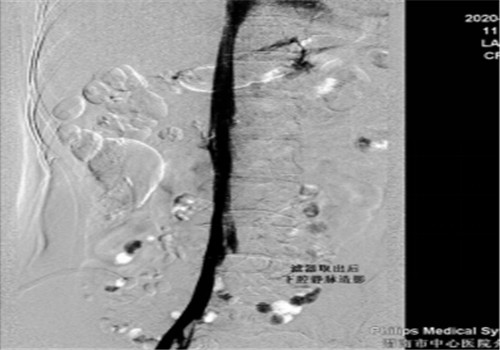

8月中旬患者来院复查,顺利骨取出科钢板,右下肢未见深静脉血栓,于8月14日行下腔静脉滤器取出术,手术顺利,历时30分钟。